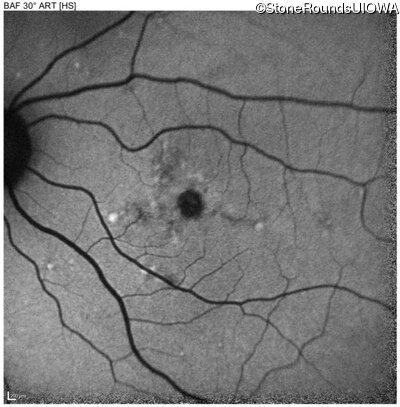

Blue Autofluorescence - Left - 20/63 -1

Exemplar